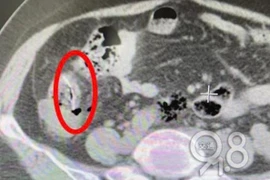

Sau khi khám, bác sĩ phát hiện bạch cầu của người phụ nữ tăng quá mức nghiêm trọng, đây là dấu hiệu cảnh báo bệnh viêm phúc mạc, trong ruột non có những mảnh dị vật, nghi là xương cá mà cô đã nuốt phải vài ngày trước.

Mảnh xương cá đi từ miệng xuống đường tiêu hóa, bằng cách nào đó đã xuyên thành ruột, tạo thành khối áp-xe dính chặt vào bàng quang, khiến bệnh nhân suýt chết.